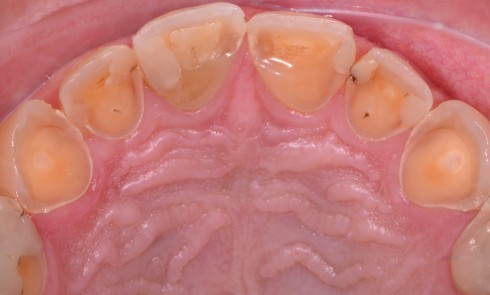

Article réservé à nos abonnés Étiologie des lésions d’usure amélaires

L’usure est la détérioration que produit l’usage. Elle est physiologique dans la majorité des cas car elle n’engendre pas de...